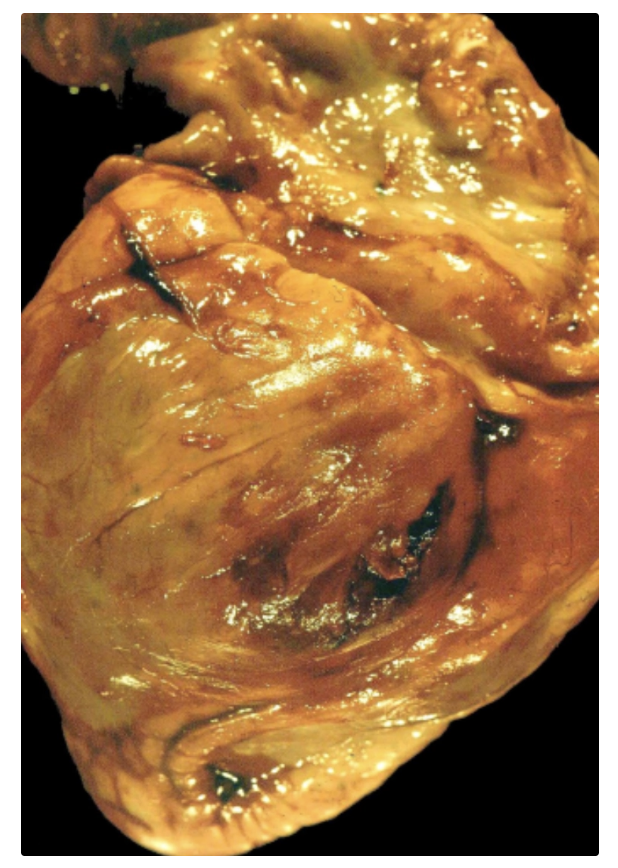

Hemopericardio: acumulación de sangre, principalmente por rotura cardiaca